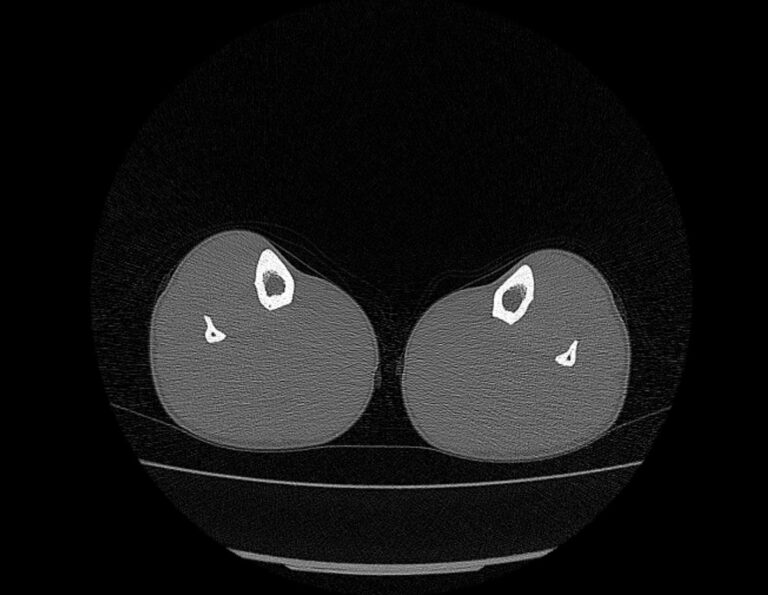

Наиболее информативным методом исследования костных структур и мягких тканей голени является мультиспиральная компьютерная томография. КТ относится к лучевым методам исследования и основана на применении ионизирующего излучения и последующей цифровой обработке данных, полученных при КТ-сканировании.

В наших медицинских центрах обследование области голени проводится на современных мультиспиральных компьютерных томографах последнего поколения TOSHIBA AQUILION. При помощи рентгеновских лучей аппараты послойно сканируют исследуемую область с толщиной среза от 0,5 мм. В результате получаются детальные снимки и цифровые трехмерные изображения в мельчайших подробностях. При этом пациент получает уменьшенную дозу рентгеновского облучения.

Мультиспиральная компьютерная томография позволяет оценить структуру костей голени, выявить переломы, воспалительные изменения, участки деструкции костной ткани, диагностировать опухолевые образования.

КТ позволяет хорошо визуализировать плотные структуры, такие как кости, благодаря их способности активно поглощать рентгеновские лучи. Чтобы улучшить визуализацию мягких тканей дополнительно применяется контрастное усиление. Для этого пациенту внутривенно вводится йодсодержащий контрастный препарат, который обладает высокой способностью поглощать рентгеновские лучи и при концентрации в патологических участках обеспечивает их яркую визуализацию на снимках КТ. С помощью контрастирования удается обнаруживать опухоли минимальных размеров, что значительно улучшает прогноз в плане лечения и выздоровления.